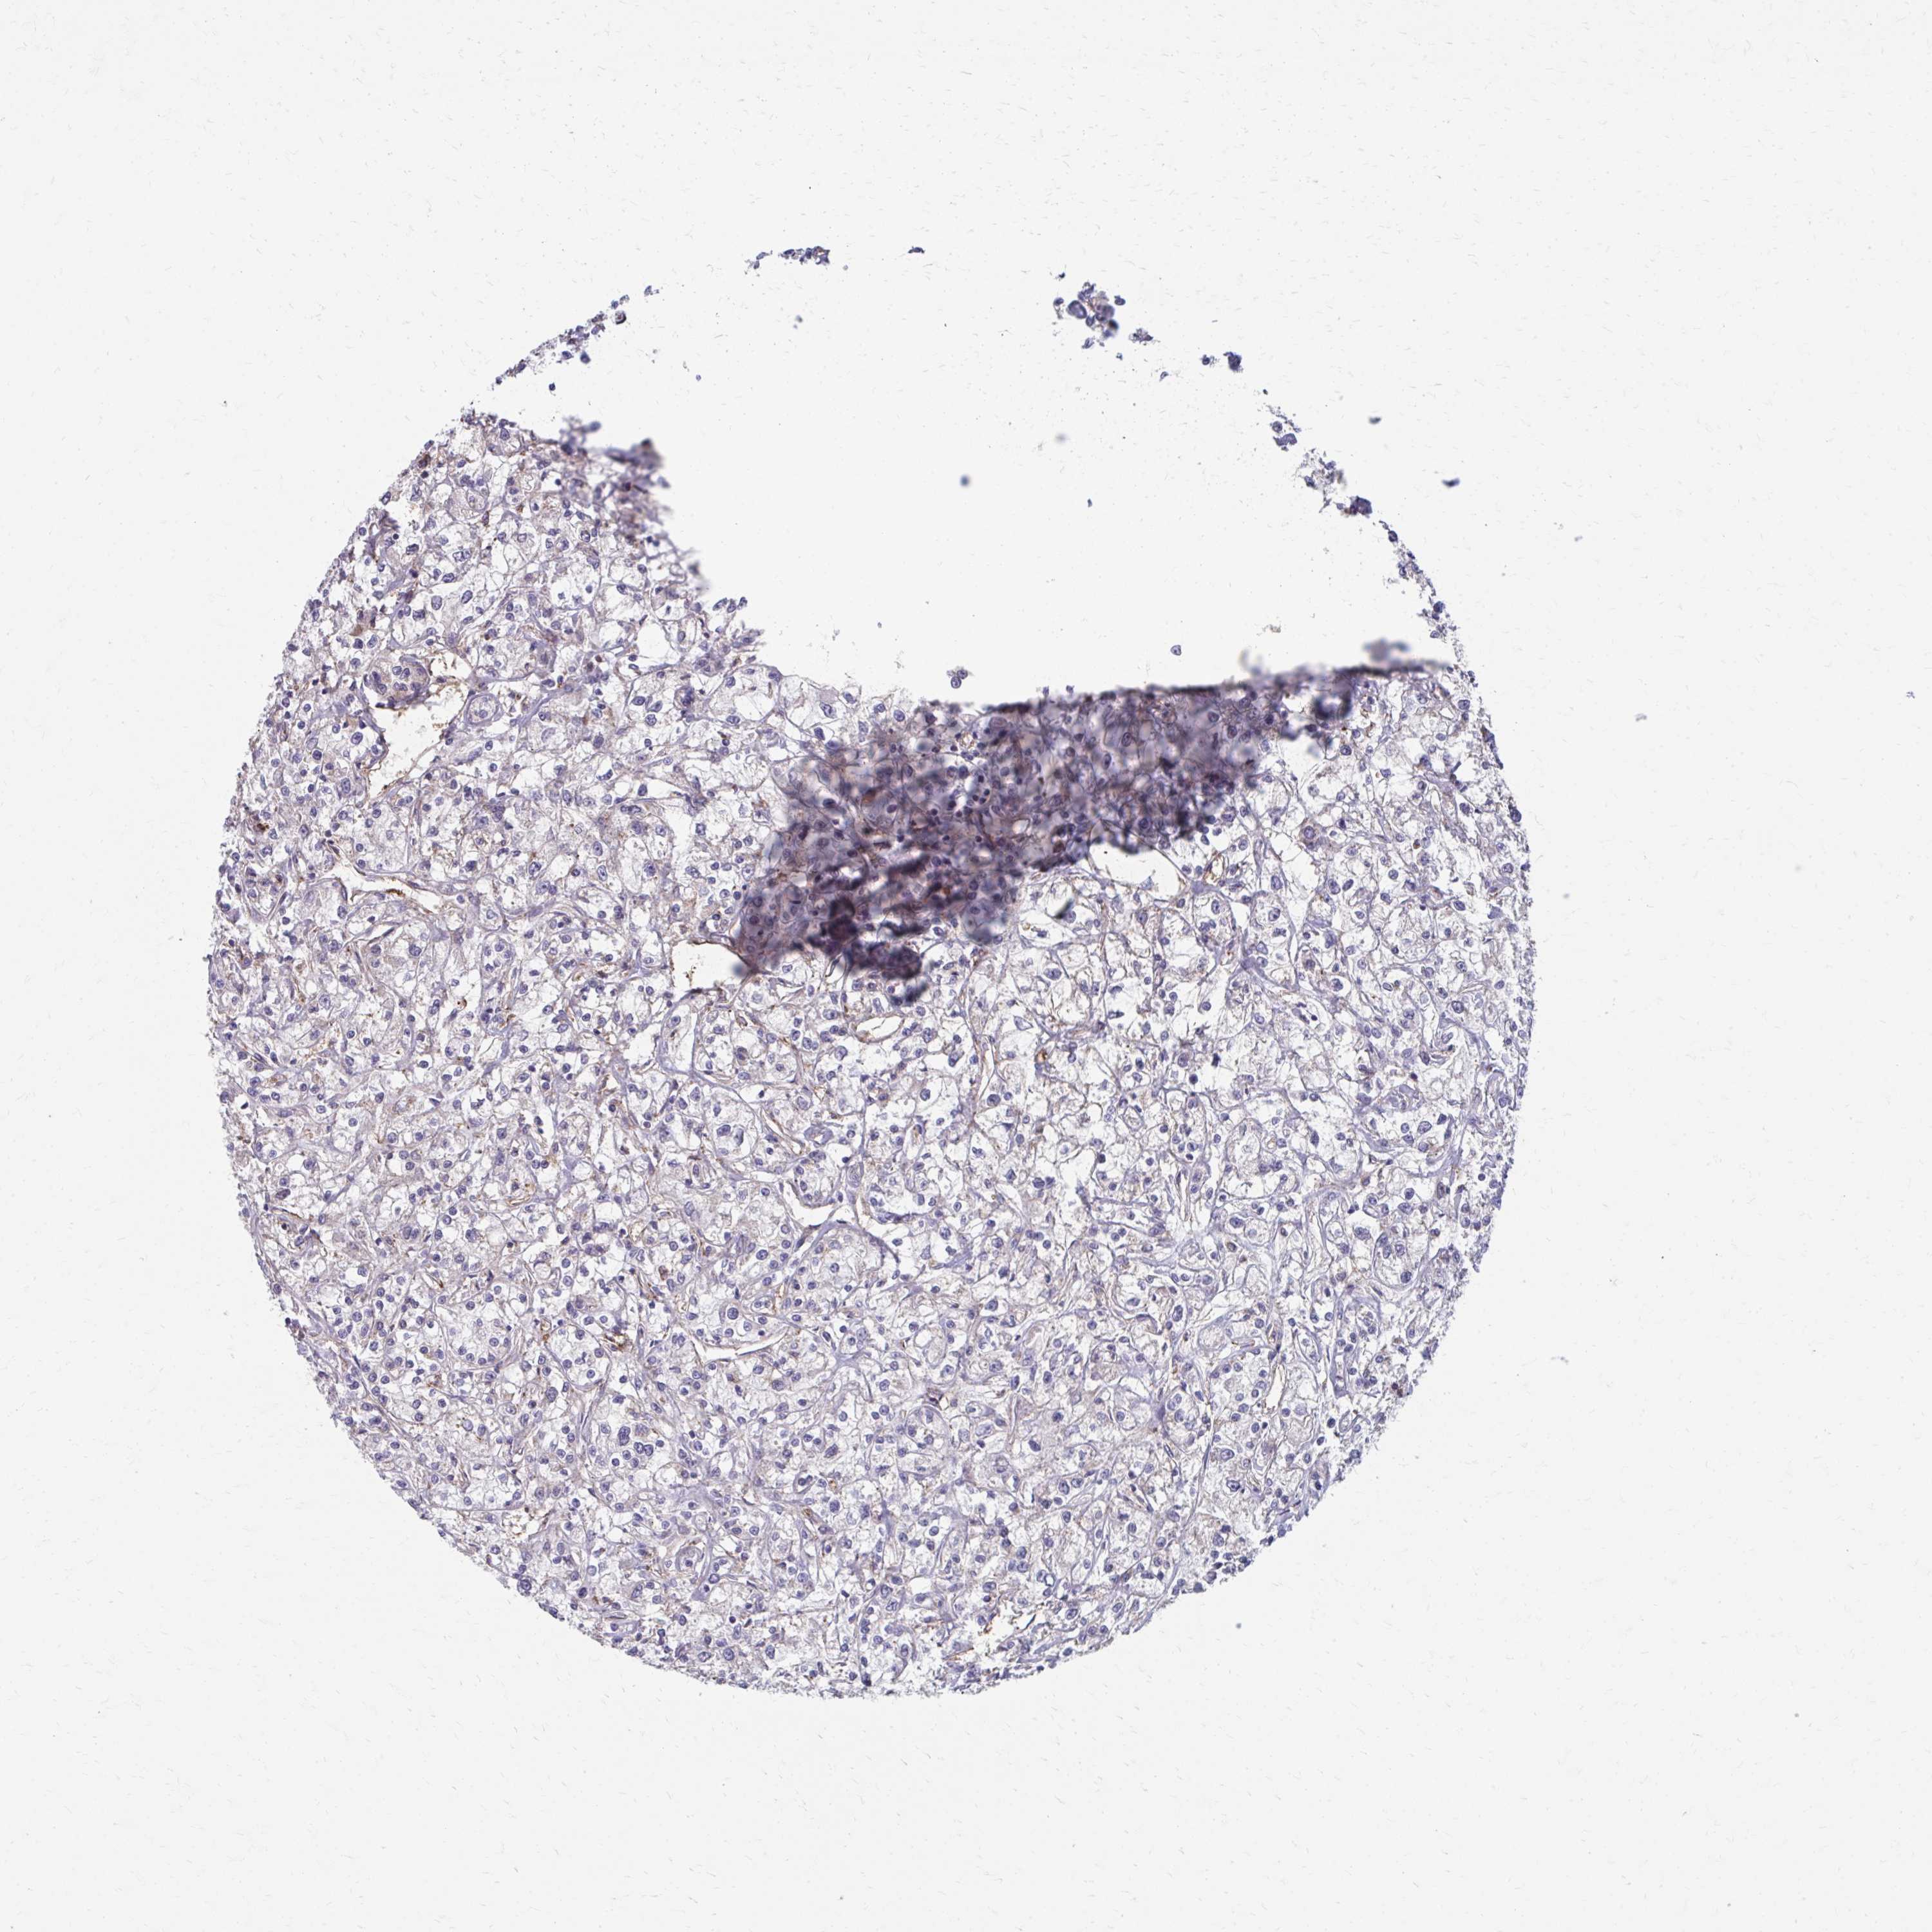

CANCER RENAL CANCER Show tissue menu

Renal cancer

Kidney renal clear cell carcinoma